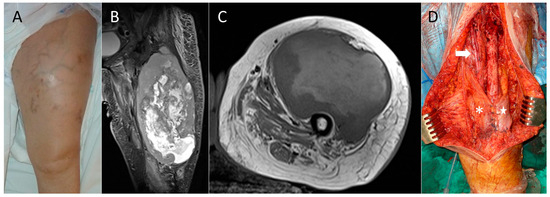

Total Quadriceps Resection in High-Grade Soft-Tissue Sarcomas of the Thigh: Surgical Technique and Long-Term Functional Outcomes in Surviving Patients

by Luis Rafael Ramos Pascua, Paula Casas Ramos, Rubén Álvarez García, Sergio Sánchez Herráez, Cristina Ojeda Thies, Maximiliano Eugenio Negri, Daniel Bustamante Recuenco and Jesús Enrique Vilá Rico

Cancers 2026, 18(1), 37; https://doi.org/10.3390/cancers18010037 - 22 Dec 2025

Background: Reconstruction of the thigh extensor mechanism following wide excision of a soft-tissue sarcoma is difficult. The aim of this study was to describe the outcomes following complete quadriceps resection for large high-grade soft-tissue sarcomas. Methods: Ten patients with AJCC grade IIIB soft-tissue [...] Read more.

Background: Reconstruction of the thigh extensor mechanism following wide excision of a soft-tissue sarcoma is difficult. The aim of this study was to describe the outcomes following complete quadriceps resection for large high-grade soft-tissue sarcomas. Methods: Ten patients with AJCC grade IIIB soft-tissue sarcomas of the anterior thigh were treated with total wide margin quadricectomy, with a mean follow-up of 4 years (range: 51–163 months) in the five surviving patients with conservative surgical procedures. The minimum follow-up period for four of these patients was 8 years. The extensor mechanism was reconstructed with local muscle transfers (eight cases) or a neurotized free flap of the contralateral vastus lateralis (two cases). Results: Four patients died, two due to non-tumor related causes and two due to metastatic disease at 50 months and 43 months. The remaining six were alive and disease-free at the final follow-up. All patients received surgical revision due to wound necrosis. Another patient required an external hemipelvectomy due to early local recurrence of the disease. Functional results of the five patients who remained alive and retained their limb were good or excellent in two cases, acceptable in one, and poor in two, according to their MSTS scores. Average knee flexion was 80° (range: 10–150°). Passive extension was complete in all cases, though no patients achieved it actively. Extensor strength was 2/5 in four patients and 4/5 in the other. Conclusion: Total quadricectomy for high-grade soft-tissue sarcomas of the anterior thigh compartment ensures wide resection margins and local disease control, although local wound complications are common, particularly in older patients. Resection appears to be technically easier if performed distally to proximally in the thigh. Local muscle transfers are more suited for low-demand patients, while neurotized free muscle flaps are mainly an option for young, motivated patients. Full article

Show Figures

Figure 1